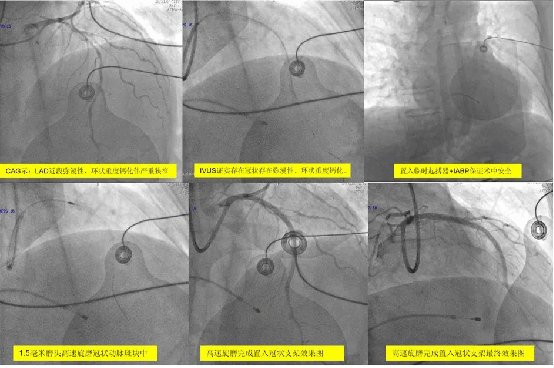

2025-12-29硬核救治 | 心血管内科四病区团队成功救治外院转诊高危患者——复杂冠脉高速旋磨联...

硬核救治 | 心血管内科四病区团队成功救治外院转诊高危患者——复杂冠脉高速旋磨联合IABP支持创造生命奇迹近日,在院领导的深切关怀与大力支持下,我院副院长赵朝、心血... -